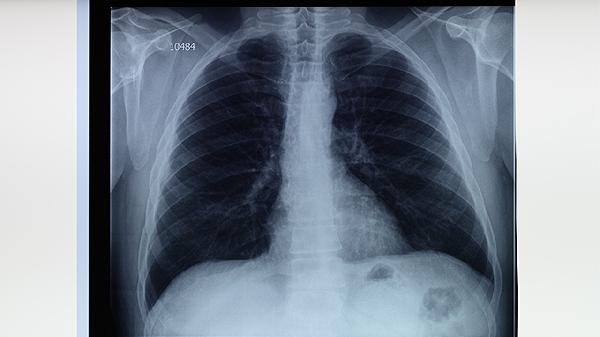

檢查肺結(jié)核的方法主要有痰涂片檢查、結(jié)核菌素試驗(yàn)、胸部X線檢查、γ-干擾素釋放試驗(yàn)、痰培養(yǎng)檢查等。肺結(jié)核是由結(jié)核分枝桿菌引起的慢性傳染病,主要通過呼吸道傳播,早期診斷有助于控制病情。1、痰涂片檢查痰涂片檢查是診斷肺結(jié)核的常用方法,通過顯微鏡觀察痰液中是否存在抗酸桿菌。該方法操作簡(jiǎn)便、成本較低,適合基層醫(yī)療機(jī)構(gòu)開展。但痰涂片檢查的敏感性較低,可能需要重復(fù)進(jìn)行以提...